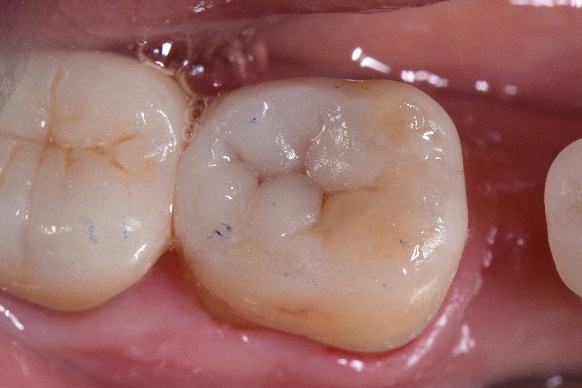

Fig. 1 Aplicarea digii și a sistemului de matrice Garrison.

Fig. 2 Îndepărtarea restaurării preexistente la nivelul 4.7.